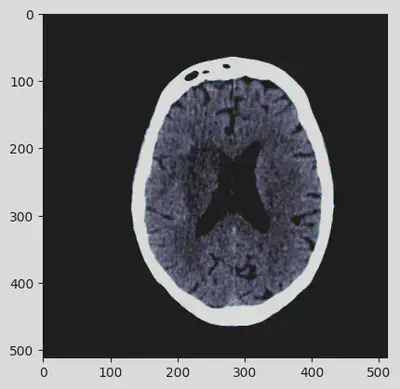

import matplotlib.pyplot as plt

arr = ds.pixel_array

plt.imshow(arr, cmap=plt.cm.bone)

<matplotlib.image.AxesImage at 0x7f5625845280>

As it is possible to see, the picture details are not well-defined so the information content is quite poor. The following additional DICOM post-processing should be sequentially performed in order to enhance the image content.

out = apply_voi_lut(hu, ds, index=0)

plt.imshow(out, cmap=plt.cm.bone)

<matplotlib.image.AxesImage at 0x7f5621ab8c40>

Got it! The sequence of pre-processing steps has deeply enhanced the details of the CT scan contained in the DICOM file. At this point, the image can be definitely visually analyzed.